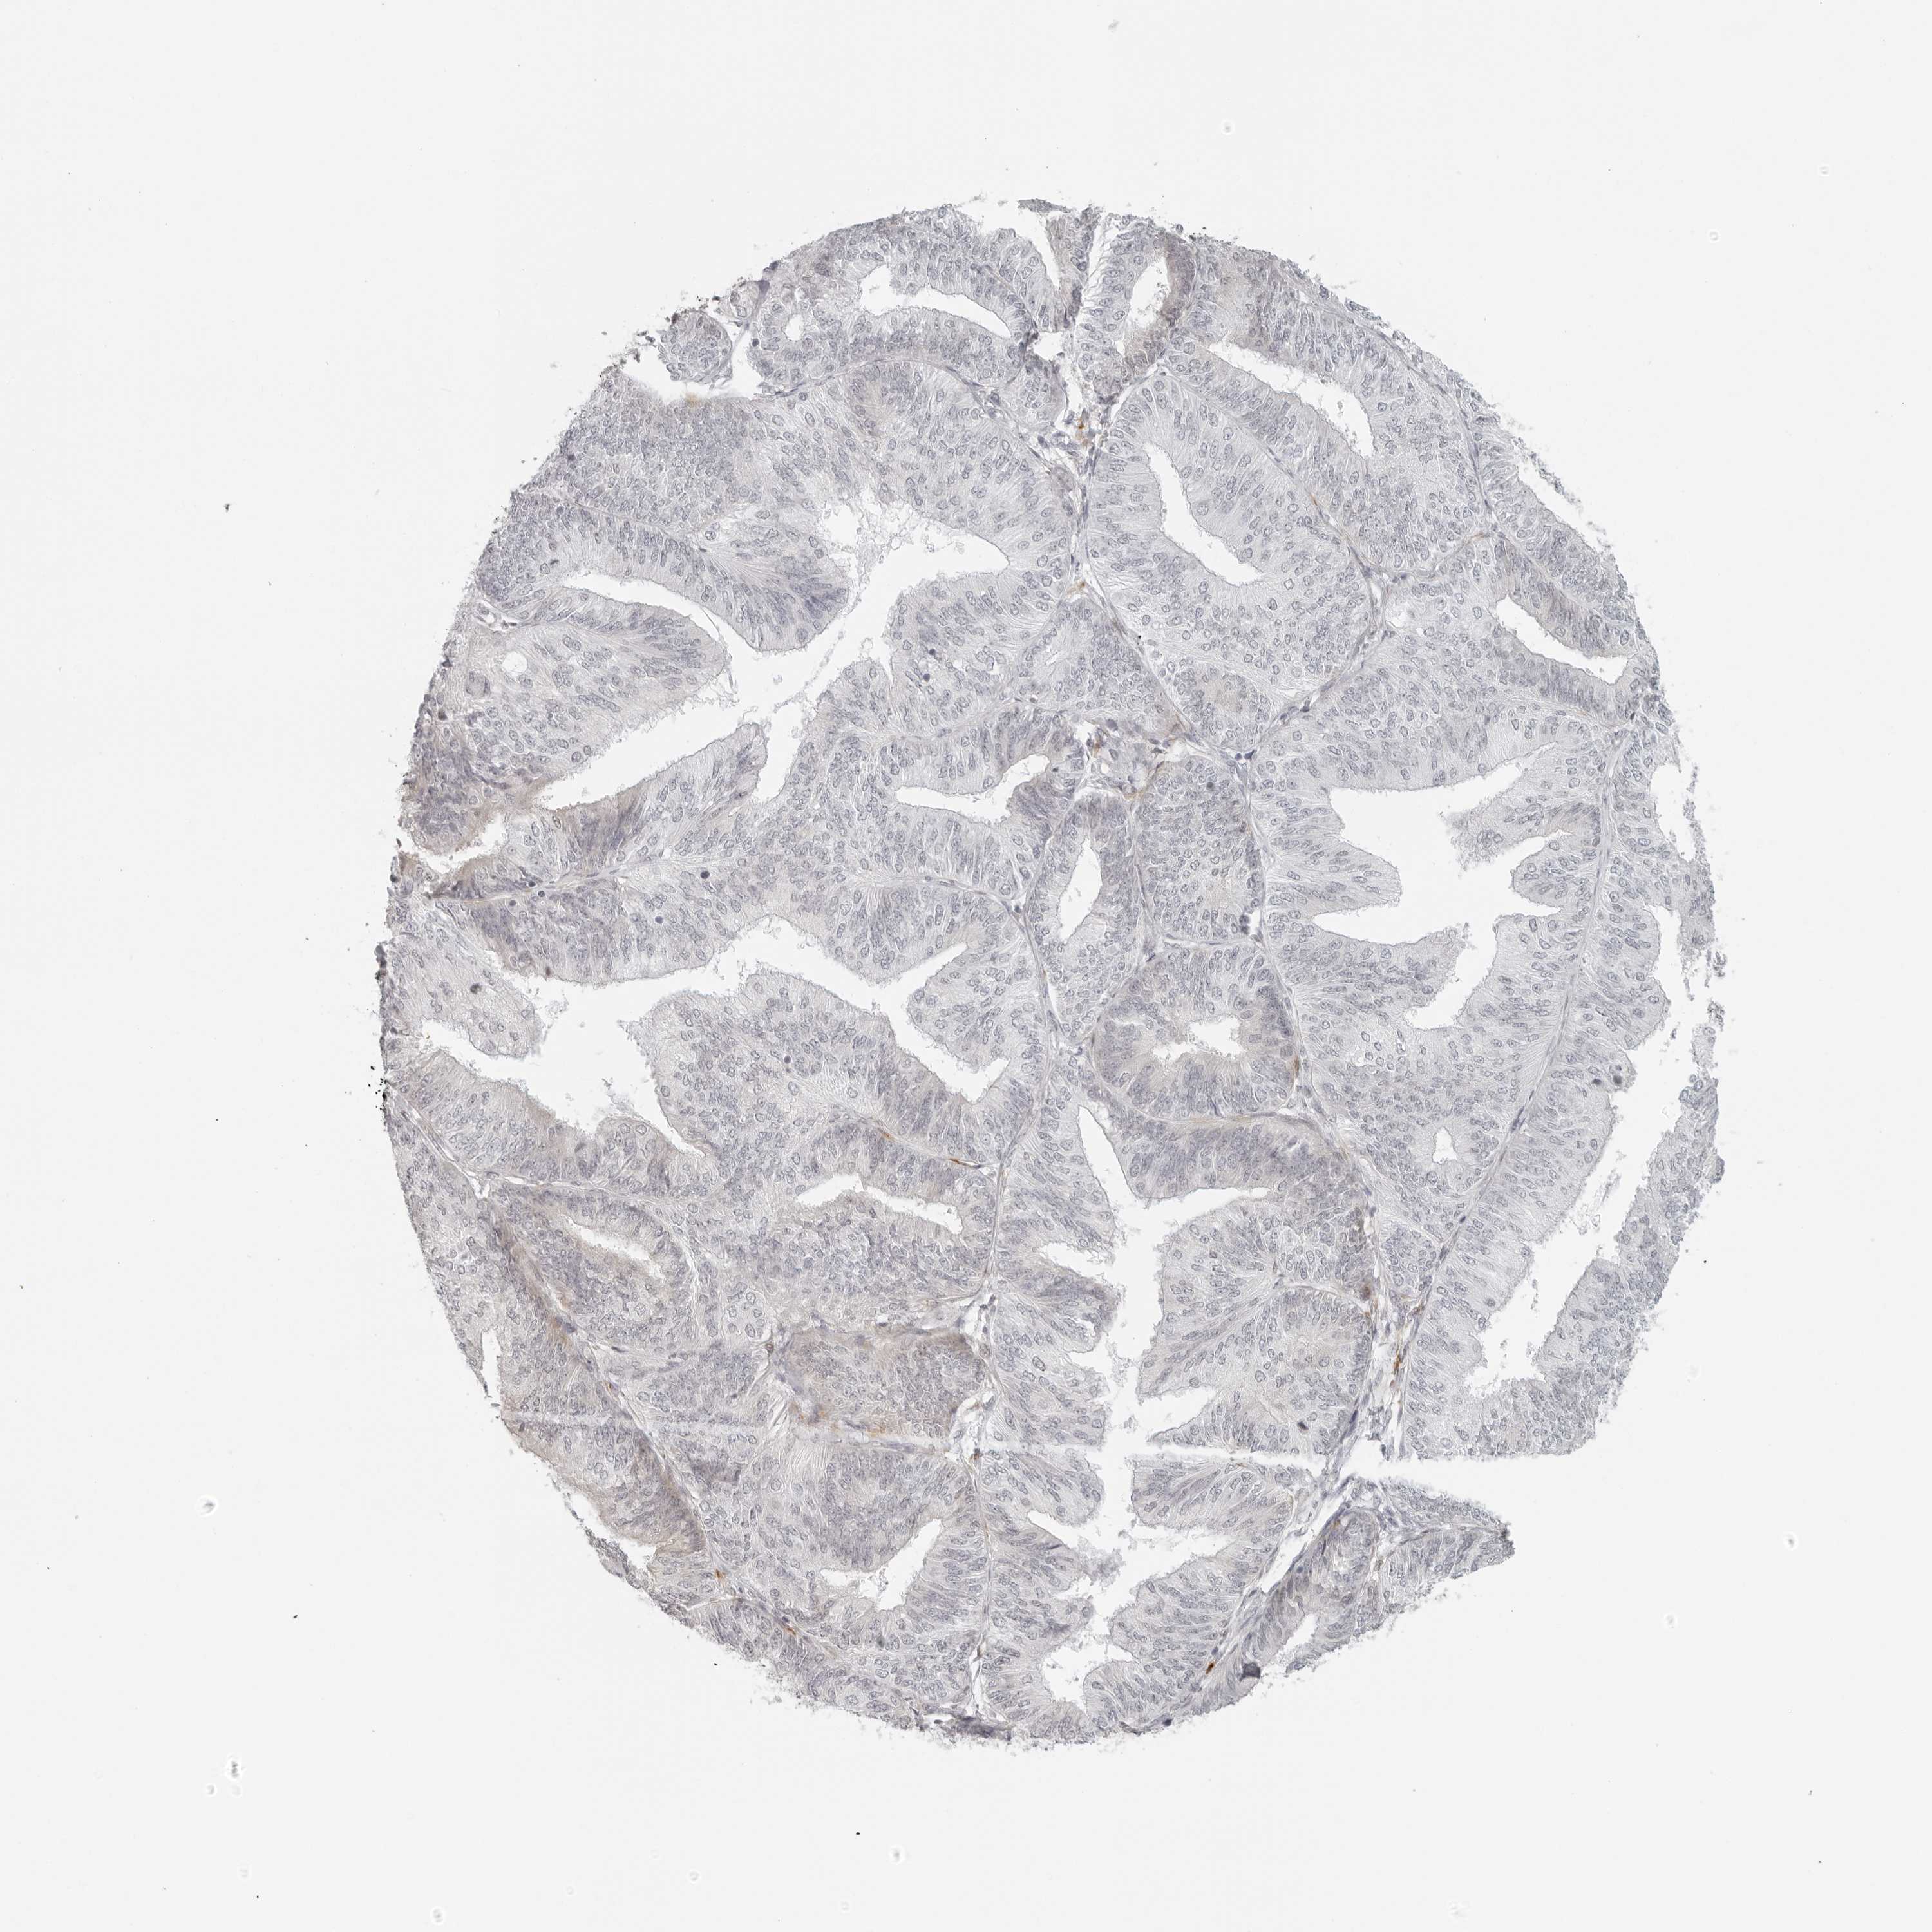

ENDOMETRIAL CANCER - Protein expressioni

A mouse-over function shows sample information and annotation data. Click on an image to view it in a full screen mode. Samples can be filtered based on level of antibody staining by selecting one or several of the following categories: high, medium, low and not detected. The assay and annotation is described here.

Note that samples used for immunohistochemistry by the Human Protein Atlas do not correspond to samples in the TCGA dataset.

Antibody stainingi

Antibody staining in the annotated cell types in the current human tissue is reported as not detected, low, medium, or high, based on conventional immunohistochemistry profiling in selected tissues. This score is based on the combination of the staining intensity and fraction of stained cells.

Each image is clickable and will lead to virtual microscopy that enables deeper exploration of all samples and also displays staining intensity scores, fraction scores and subcellular localization as well as patient and tissue information for each sample.

Antibody HPA028507

Staining

High

Medium

Low

Not detected

Intensity

Strong

Moderate

Weak

Negative

Quantity

>75%

75%-25%

<25%

None

Location

Nuclear

Cytoplasmic/membranous

Cytoplasmic/membranous,nuclear

Adenocarcinoma, NOS

Adenocarcinoma, metastatic, NOS